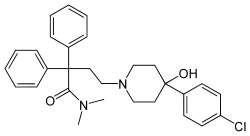

Others

Structures

| Other open chain opioids | ||||

|---|---|---|---|---|

|

|

|

| |